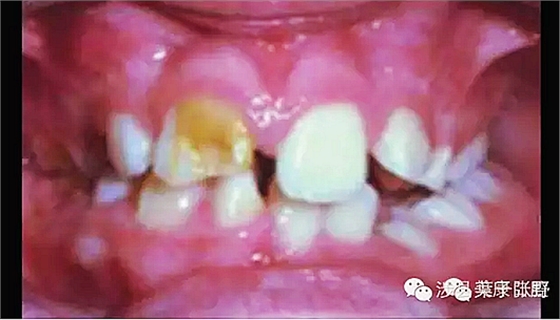

影響美觀,讓小朋友笑話。

![SGTCU9W{CJ(KNO938]DJZ[Q.png SGTCU9W{CJ(KNO938]DJZ[Q.png](/Mobile/UploadFiles/FCK/2017-04/6362664285172919675298344.png_280.jpg)

影響咬合高度建立